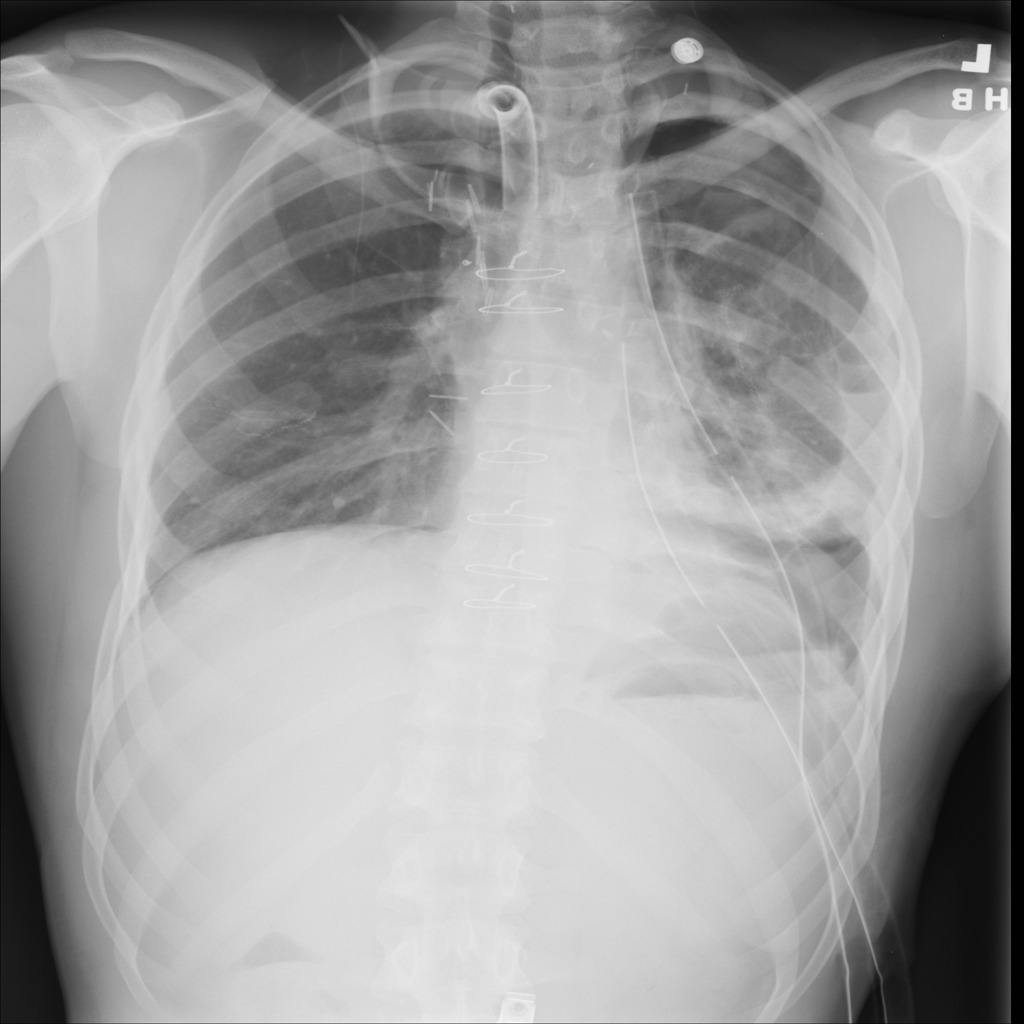

Showing up to 90 reference images for Pneumothorax.

PAT-FD18 · IMG-000Pneumothorax

PAT-FD18 · IMG-000

AP